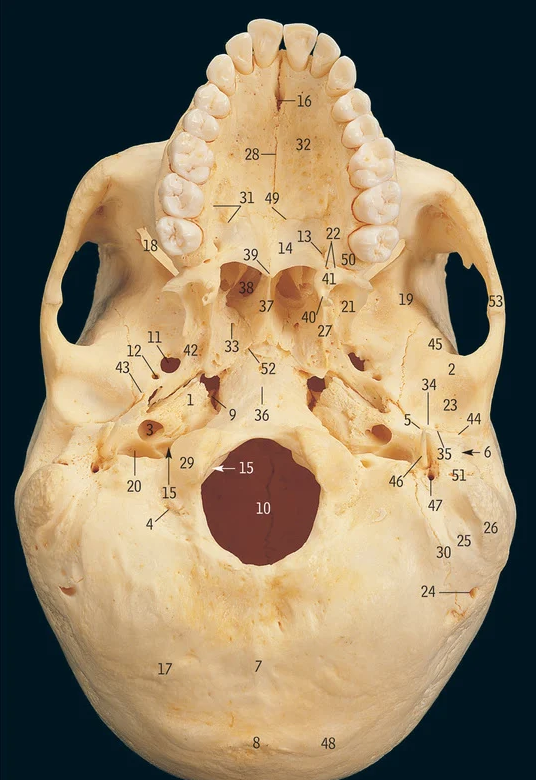

Superior nasal concha

19

Middle nasal concha

1

Ethmoidal air sinuses

6

Frontal air sinus

11

Lateral pterygoid plate

13

Medial pterygoid plate

Supra-orbital notch

29

Occipital condyle

48

Superior nuchal line

37

Zygomatic process of temporal bone

What muscle attaches to the zygomatic process of the temporal bone

18

Mastoid processÂ

Petrous part of temporal bone

28

Internal auditory meatus

9

Mandibular fossa

3

Carotid canal

46

Styloid process

47

Stylomastoid foramen

What is circle in blue

Inner ear

16

Middle ear

What is X

Foramen for emissary vein

Nasal bone